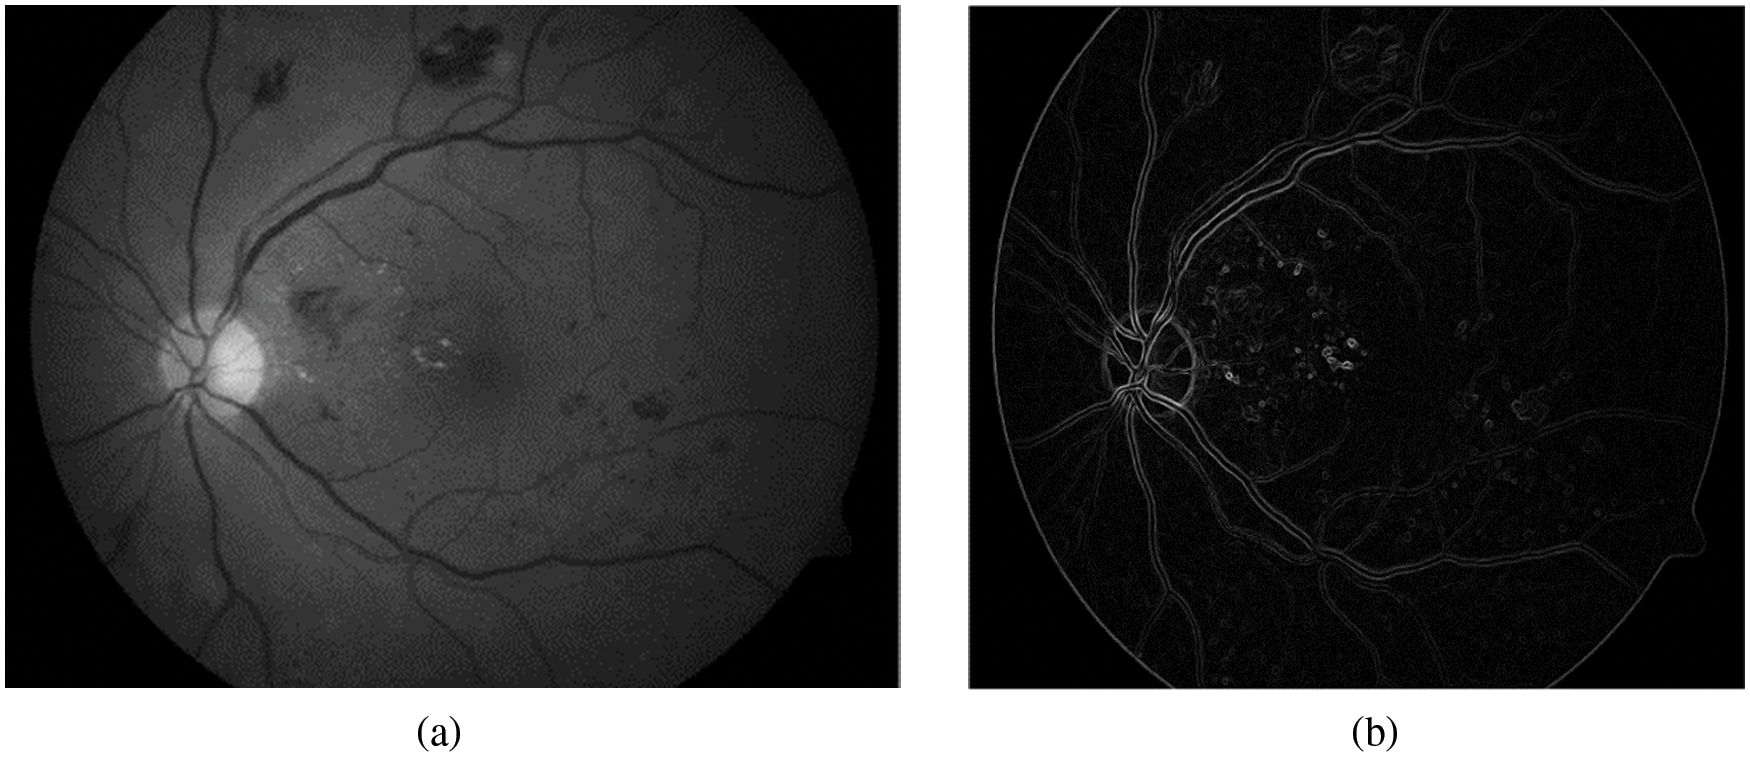

where p(x, y) represents the new intensity value of the current pixel P, avg(…) represents to the average value. Fig. 3b illustrates the extracted blood vessels.

Figure 3: Segmentation of blood vessels (a) Green retinal image. (b) Blood vessels after removal background